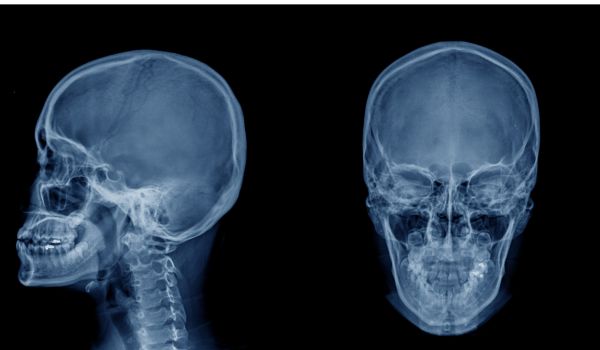

Радіологічна діагностика скроневої кістки

Радіологічна діагностика скроневої кістки: Ключові аспекти для роботи рентгенолаборанта